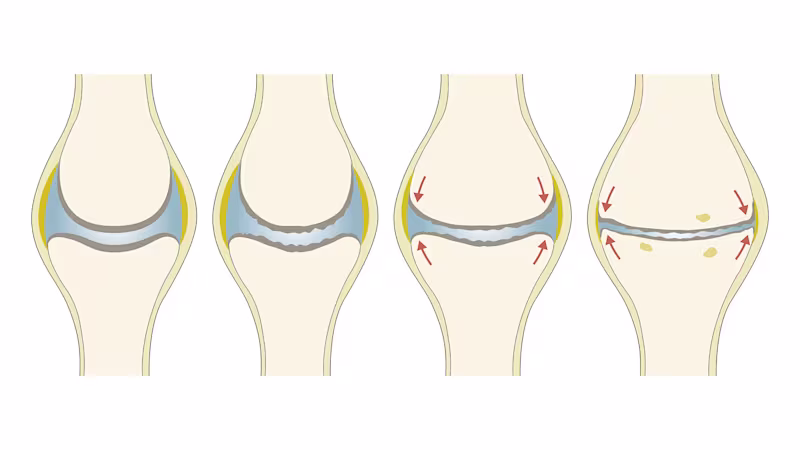

Disease progression: Stages of osteoarthritis

Osteoarthritis of the knee is classified into four degrees of severity:

Osteoarthritis degree 1:

The joint cartilage has invisible signs of wear. It is less elastic than healthy cartilage and cannot recover well after being subjected to load. Initial knee pain may occur under high load.

Osteoarthritis degree 2:

The cartilage tissue becomes thinner. The cartilage surface becomes rough and uneven. The bones form initial spurs (osteophytes). The knee is considerably less able to bear weight. At this stage of osteoarthritis, the progression of the disease can be effectively slowed by exercises, weight loss and medical devices such as braces.

Osteoarthritis degree 3:

The cartilage has partly disappeared so that the bones begin to rub against each other in some places. X-rays show pronounced bone spurs and narrowing of the joint space. At this advanced stage, osteoarthritis causes considerable movement restrictions and knee pain.

Osteoarthritis degree 4:

The joint space has narrowed considerably and the joint cartilage has almost completely disappeared. The bones are often damaged. The joint is deformed and often inflamed. In this final stage, joint-replacement surgery – i.e. a prosthetic knee joint – may be the best solution.